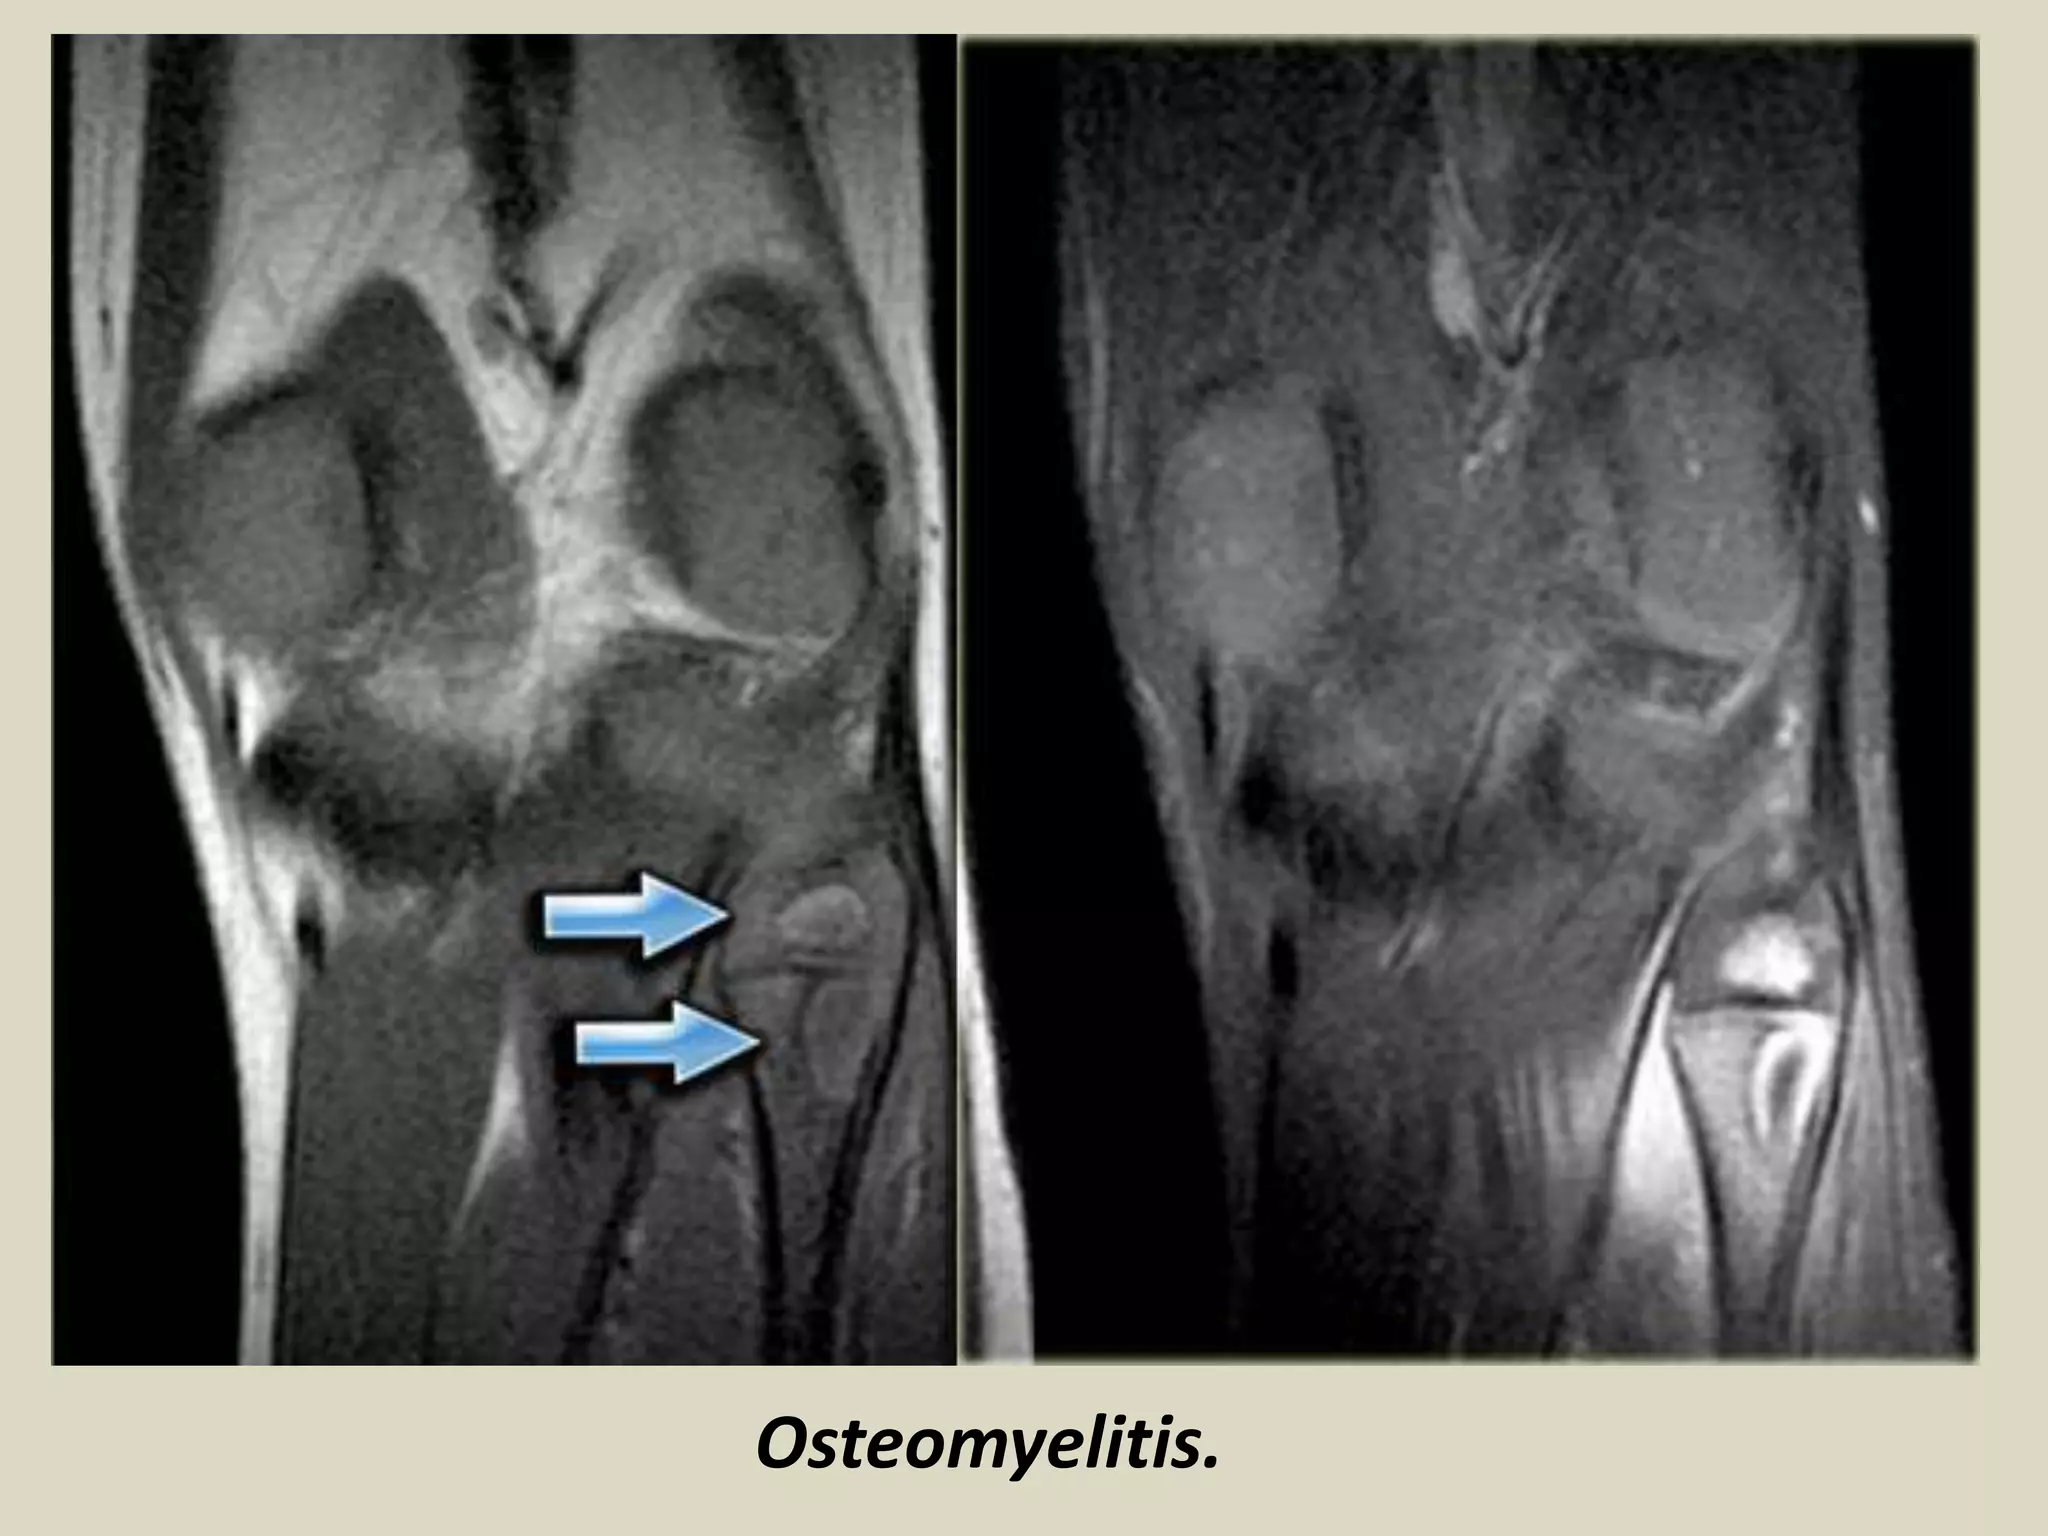

OSTEOMYELITIS

Definition:

Inflammation of bone and marrow also known as infection of bone

May manifest as a primary solitary focus of disease or as a complication of other systemic

disease.

May be caused by different bacterial organisms

Types of osteomyelitis:

Pyogenic Osteomyelitis

Hematogenous osteomyelitis commonly occurs in children.

Staphylococcus aureus is the most common organism responsible for pyogenic osteomyelitis

H. influenzae & group B streptococci are frequent pathogens in neonatal infection.

Gram negative organisms are isolated from patients with genitourinary infection or who are

IV drug abusers

Almost always caused by bacteria.

Organisms reach to the bone by:

1 hematogenous spread

2 extension from a contiguous site

3 direct implantation

The latter (3) occurs as a complication of a compound fracture or of surgery.

Symptoms:

High fever, localized pain and swelling

Labs:

high white cell count, high ESR.

Radiology:

Lytic focus of bone destruction with peripheral zone of sclerosis and reactive

periosteum.

Hot spots on bone scan.

MRI: increased signal intensity in the medullary space.

D.D.: small round blue cell tumor

Chronic osteomyelitis:

One week after the infection, host response evolves with infiltration by chronic

inflammatory cells and release of cytokines which in turn stimulates osteoclastic

bone resorption, ingrowth of fibrous tissue and reactive new bone formation.

Reactive bone in the form of a living tissue around the segment of necrotic bone

(sequestrum) is known as involucrum.

Variants of osteomyelitis:

Brodie abscess – small intraosseous abscess that frequently involves the cortex

and is walled of by reactive bone. It may mimic tumor.

Sclerosing osteomyelitis of Garre affects the jaw bone with extensive new bone

formation.

Chronic Recurrent Multifocal Osteomyelitis.

Osteomyelitis - Bone Infection

Femoral Osteomyelitis.

Osteomyelitis.